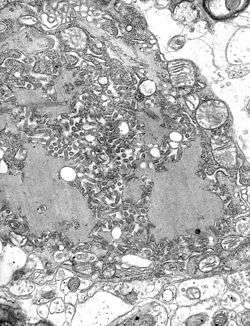

Trafficking-of-Dendritic-Cells-within-the-Brain-during-Toxoplasmic